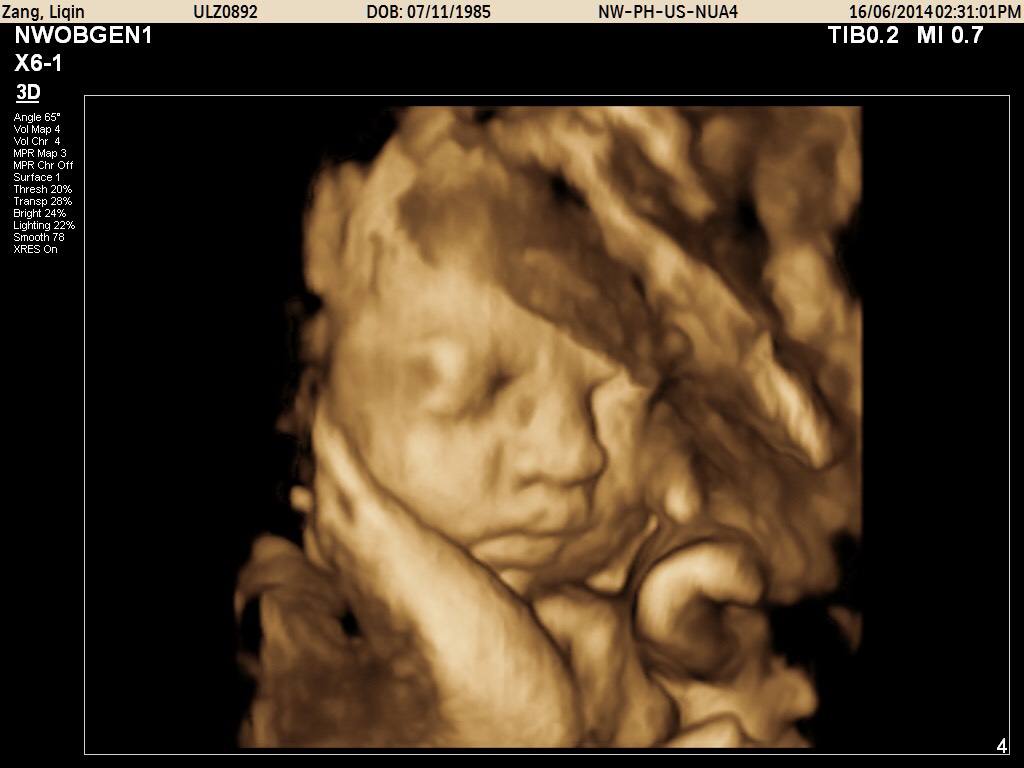

四维彩超就像我们平时看的3D电影一样,让医生看到子宫内胎儿更为直观、立体的影像。大部分的胎儿四维照显得很丑,或者嘴巴大鼻子大,原因有以下三点。

毕竟四维彩超目的是排畸,医生通过全方位及多切面扫孕妈的腹部,区别测量获得宝宝的头围、双顶径侧面、眼眶横切面、唇冠状、左右室流出道切面等等,所以医生会选择放大这部分的特征以仔细查看,顺便就把胎儿的面部特征拍下来了,“送”给父母。非专业人士就看到宝宝的嘴巴和鼻子特别大,所以比较奇怪。

胎儿在子宫内被羊水包裹,而且将自己的部分排泄废物排到羊水中去,胎儿皮肤上会有一层胎脂,是来保护胎儿肌肤不受羊水伤害的。而胎脂的表面并不光滑,而且并不是均匀分布在皮肤上,若是嘴巴鼻子周围胎脂较多,再加上羊水的放大作用,就会显得胎儿的嘴巴和鼻子特别大。从四维照上可以看出,胎儿头面部位都是凹凸不平的状况,有人戏称好像外星人,那就是胎儿表面的胎脂。